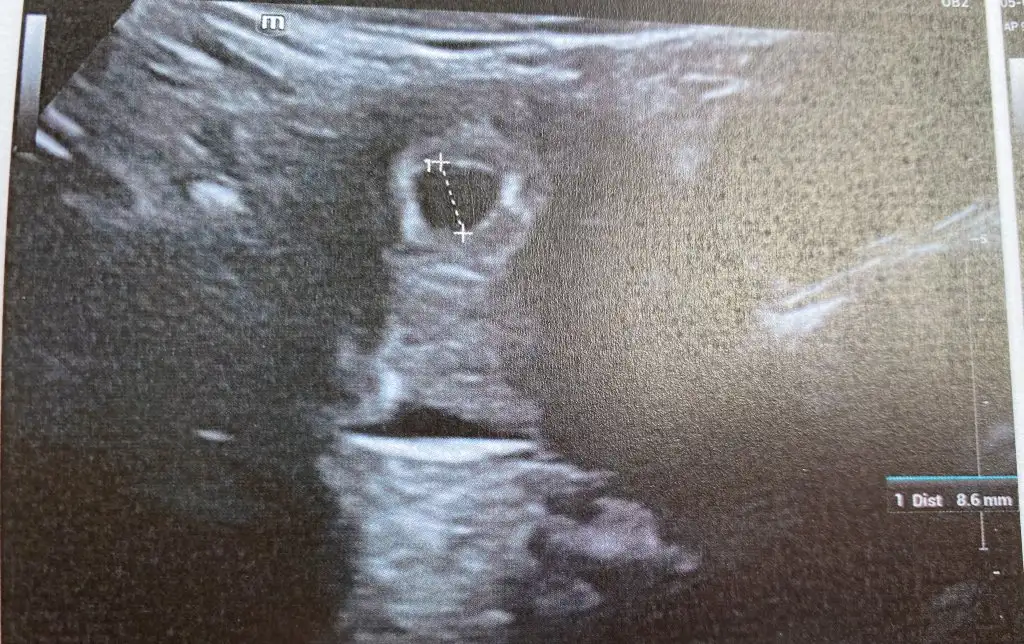

Benim de sat 22 Mart. Cuma günü gitmiştim doktora. Sata göre 6+2 ydim. Siz de 6+3 olmanız gerekiyor doktora gittiğiniz gün. Benim kesem 8.6 mm idi ve doktora kese için çok iyi dedi. Biz de yolk ve bebek göremedik ama doktor olumsuz konuşmadı ve haftaya gel dedi. Sizin neden kese için haftayla uyumlu değil demiş doktor acaba? Ultrason resmi var mı acaba?

Evet. Okudum sizin konunuzda. Benim sat 22 Mart. Kese 8.6 mm. Doktor iyi dedi.

Sizin sat 18 Mart. Kese 9 mm. Haftayla uyumlu değil demiş.

Yani benim değerleri baz alırsak senin uyumunda iyi gibi. Bir dahaki randevunuz ne zaman?

Ben de perşembe günü gideceğim. İnşallah görürüm bebeği ve kalp atışını. Benim ultrason görüntüsü böyleydi

bak o işaretledigim alandakş yuvarlak var ya o yolk sac o olustuysa bebek de var daha minik burda ondan gözükmemiş haftaya kesin görürsün yolk sac bebek olusmadan olusmaz zTen

bak bunu netten aldım o soldaki yuvarlak yolk sac sende de aynısı var sadece sendeki cihazın çözünürlüğü düşük o yüzden bu kadar net değil